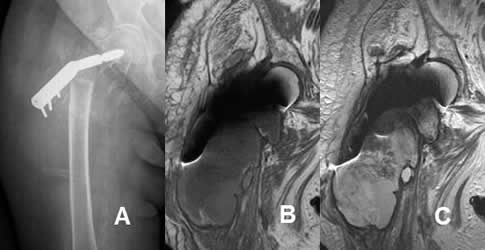

Fig 115. Mala posición del material.

A: Rx AP: Desplazamiento del tornillo de compresión, colocado en la cabeza femoral.

B: RM coronal en T1 y C: RM coronal en T2. Colección de tejidos blandos, hipointensa en T1 e hiperintensa en T2.